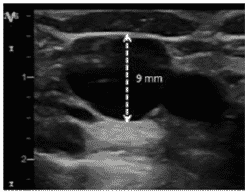

Determinar el calibre de la vena

La determinación del calibre es esencial, no solo porque aumenta la probabilidad de punción única exitosa, sino también porque el calibre determinará el tamaño del catéter.

En líneas generales, la mayoría de las guías recomiendan que el catéter no tenga un grosor mayor de 1/3 del diámetro de la vena (1 French equivale a 0.33 mm) para prevenir el riesgo de trombosis.

Para determinar el calibre se empleará el modo 2D y la función “regla”, “diámetro” o su equivalente según le modelo de ecógrafo. Una vez en este modo, el operador se dispondrá a colocar el cursor en la parte superior y medial de la pared de la vena; posteriormente trazará una línea recta hasta llegar al borde opuesto de la pared, obteniéndose, así, el diámetro antero- posterior.